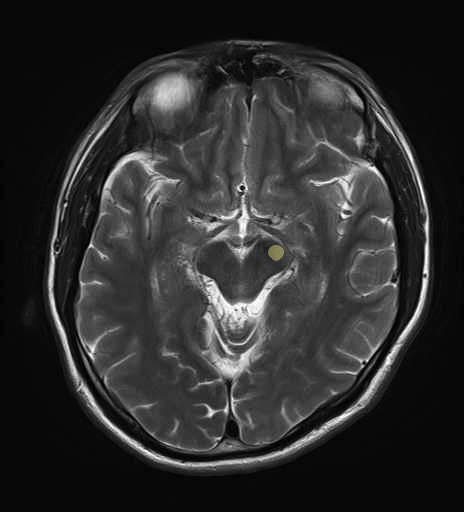

運動系 錐体路系に色を付けました。

■皮質脊髄路(いわゆる錐体路):一次運動野から脊髄遠隔の下位運動ニューロン細胞体まで

■皮質核路:一次運動野から橋及び脊髄神経核まで